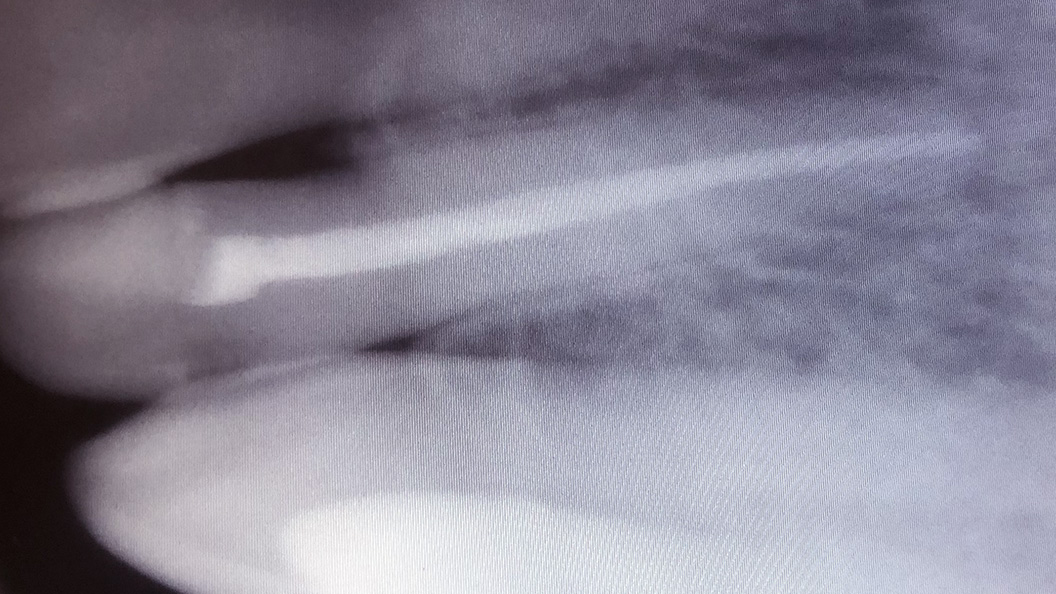

До и после лечения

Пациент обратился в «Стоматологию Комфорта» с жалобой на острую длительную боль от холодного в зубе 1.2 — верхний резец. Врач Абдураманова Марина Ягьяевна провёл обследование и диагностировал обострение хронического пульпита. Проведено эндодонтическое лечение зуба 1.2 с пломбировкой канала и временным восстановлением коронковой части. Рекомендована установка постоянной ортопедической конструкции.

Ход лечения:

- введение анестезии;

- изоляция зуба коффердамом;

- эндодонтическое лечение верхнего резца;

- постоянная пломбировка канала;

- временное восстановление коронковой части.